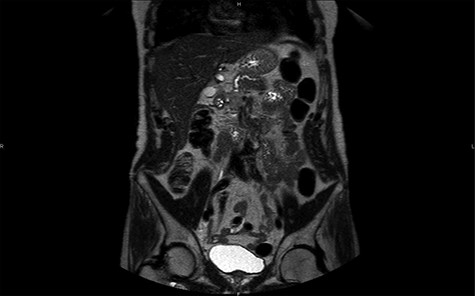

Magnetic resonance imaging (MRI) confirms the hypervascularized and atypical character of this pancreatic tumor (Figs 2 and 3). Moreover, one hepatic lesion with the same characteristics is highlighted.

MRI in coronal section, T2 phase: visualization of a compression of the main pancreatic duct.